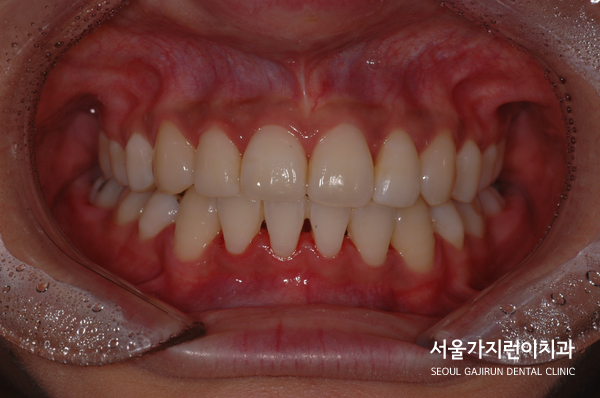

환자분이 진행한 치아교정은 설측탄댐교정방식이었는데요. 치아의 쓰러짐 없이 안정적으로 자리를 찾았고 미니스크류를 더해 정교한 컨트롤이 진행되었습니다. 사진을 보면 중심선도 맞고 뻐드러진 돌출감도 많이 해소되었는데요. 전체적인 치열이 잘 정돈된 것을 확인할 수 있었습니다.

자연스럽게 미소를 띄는 환자분! 돌출감이 심한 덧니 치아교정도 콤비교정, 설측교정으로 개선 가능하니 더 자세한 과정은 아래의 블로그를 통해 확인해보시기 바랍니다. 환자의 정밀한 상태 분석을 통해 교정노하우를 더하면 재발 걱정없이 치아교정을 마무리할 수 있겠습니다.